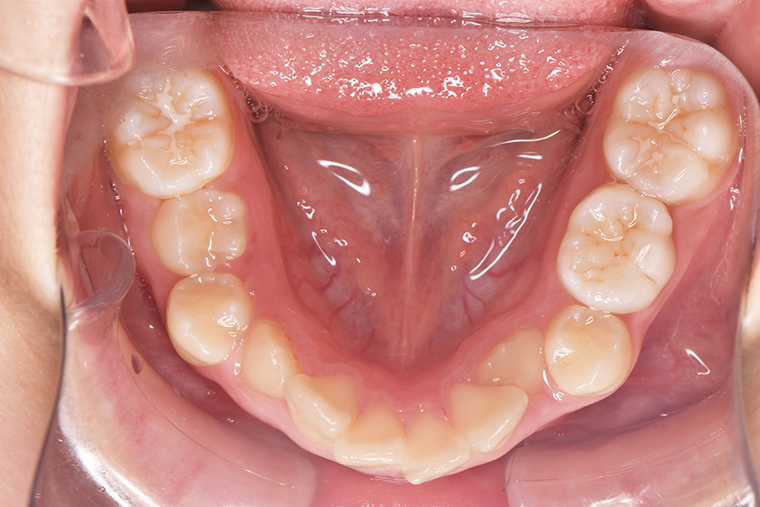

Case Study9歳女性ガタガタな歯のマウスピース矯正-矯正期間1年6ヶ月